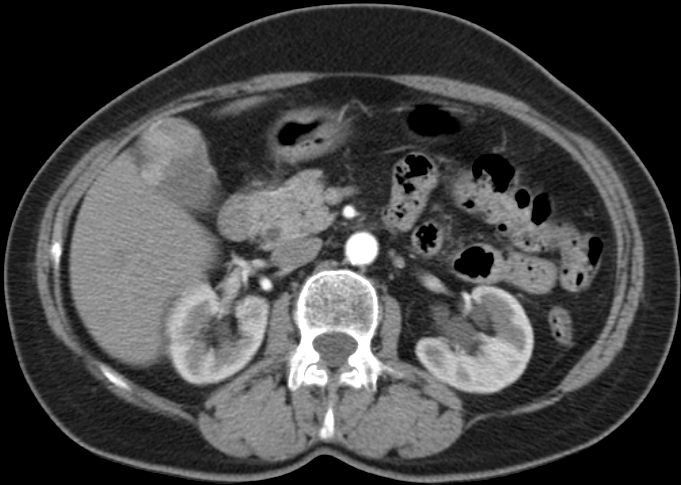

89-jährige Frau mit Infektzeichen. Zunächst sonographisch Verdacht auf Gallenblasenempyem. Im CT ein Gallenblasenkarzinom mit Leberinfiltration. Wegen Alter und AZ palliative Versorgung. | ||